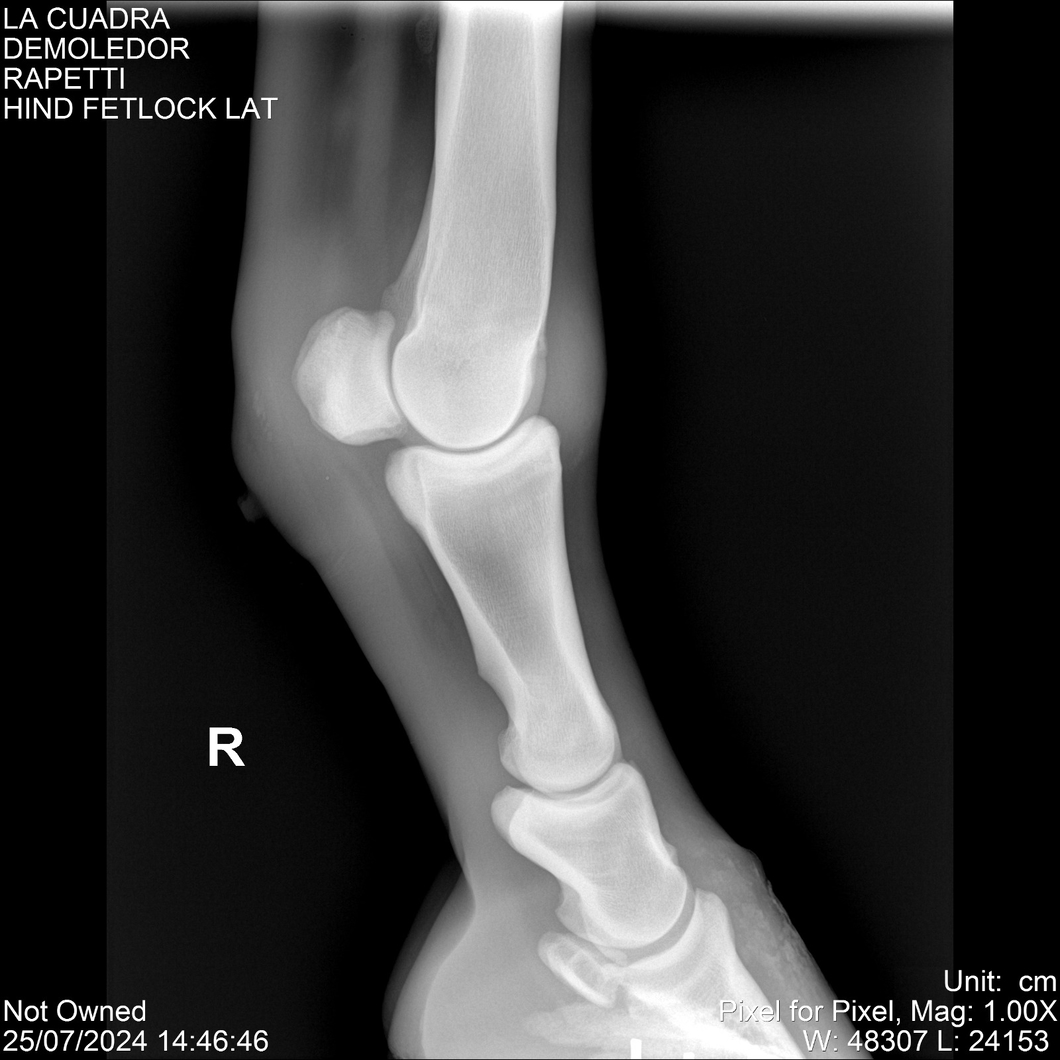

LOTE 14, DEMOLEDOR 🔥 🔥 🔥 Lote Anterior Volver al remate Lote Siguiente Ficha Contacto Montevideo - Ficha del Lote Identificador: #284454 Categoría: Yeguarizos Montevideo - 89 Visualizaciones ClicData Contacto Empresa: Abelenda N. R., Walter Hugo Nombre*: Teléfono* : E-mail* : Mensaje Enviar Registrese gratis Este contenido Exclusivo está disponible sólo para usuarios registrados Ingresar